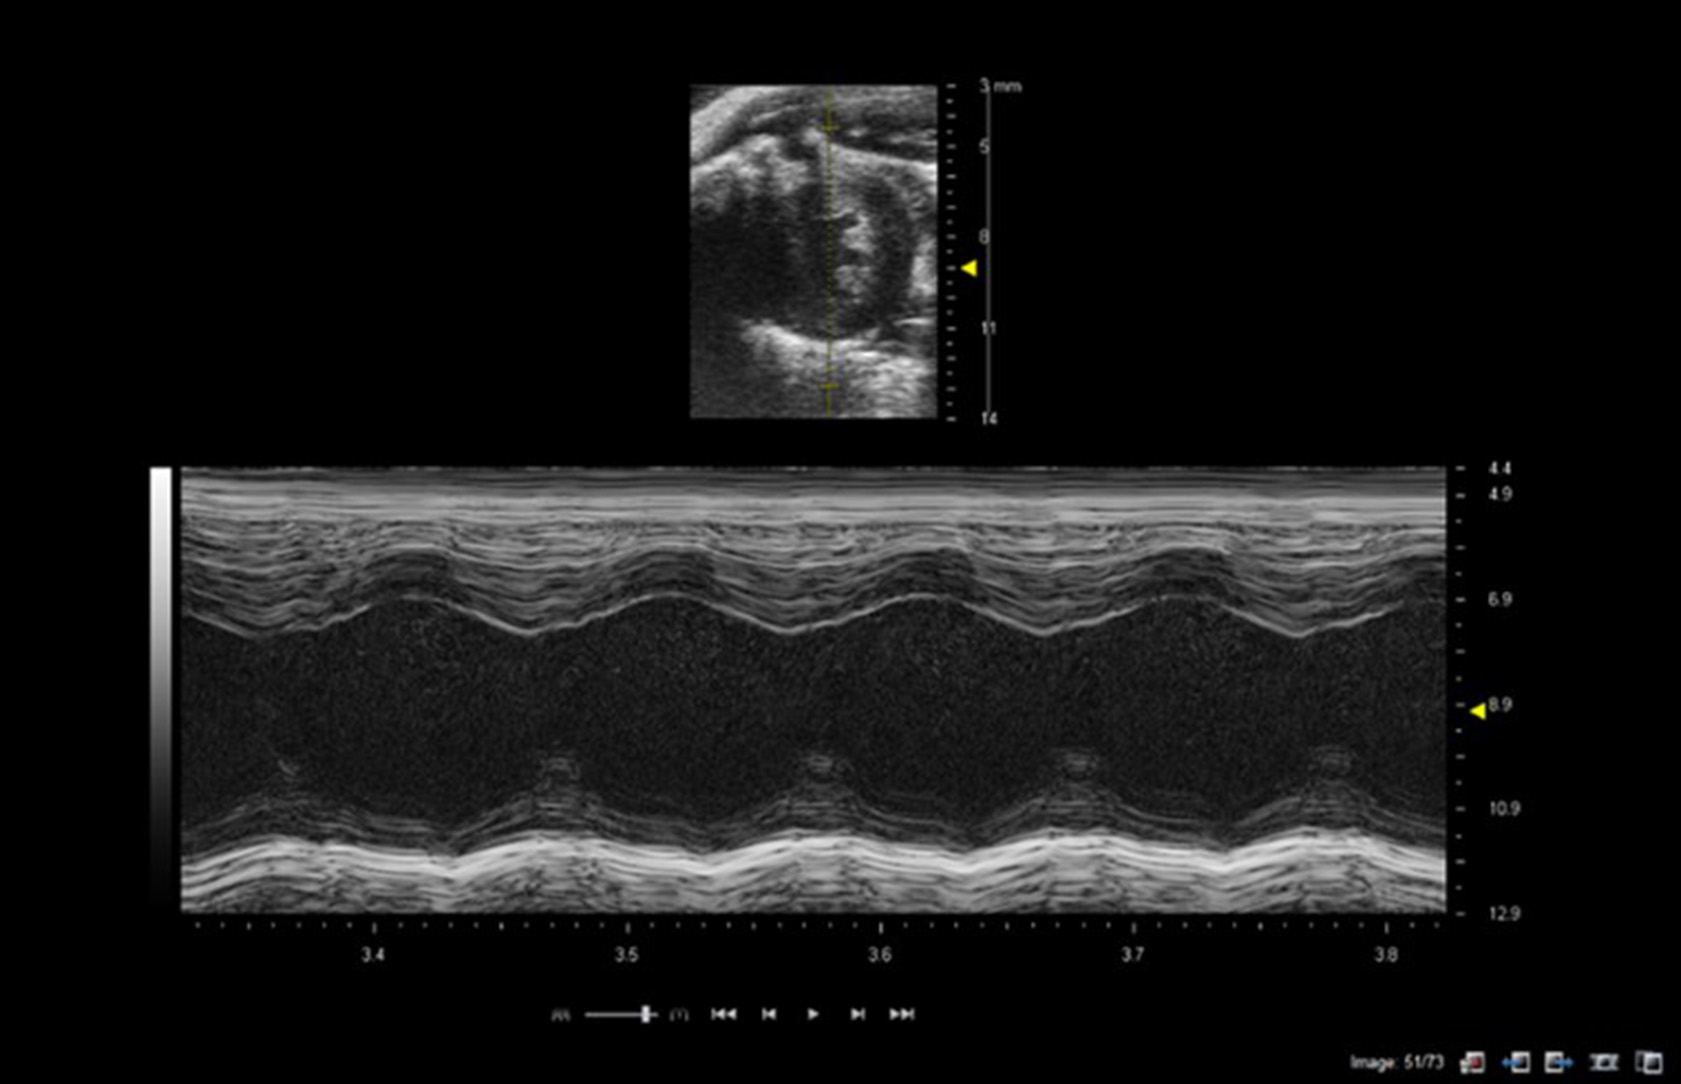

M-Mode Imaging

M-mode imaging or motion-imaging is used principally to study fast moving structures such as heart-wall movement or valvular movement. A single line is selected in the B-mode image intersecting the chamber walls or valves of interest and ultrasound data is acquired only along the pre-selected M-mode line. Consequently data is acquired with high temporal resolution, as only one line of data is acquired rather than 128 lines of data in a full B-mode image. The M-mode data is displayed as a continuous function of time scrolling across the screen with depth on the y-axis and time on the x-axis (Figure 2).

Figure 2. M-mode of mouse heart showing short-axis B-mode image in top half of image with M-mode line selected (yellow line in image). Lower image shows M-mode trace through the left ventricle at level of papillary muscles. Images acquired using a 40 MHz probe focussed at 9 mm depth.

M-mode is especially useful for the measurement of the maximum and minimum dimensions of the ventricles for calculation of cardiac indices such as fractional shortening and for the assessment of myocardial wall abnormalities (Figure 2). However, M-mode measurements of chamber size should not be used for measurement of cardiac indices derived from volume measurements (e.g., ejection fraction) as these make assumptions re the shape of ventricles which are prone to error especially for animal models which have suffered myocardial infarctions and for which the shape of the ventricle can undergo deformation and remodeling. M-mode imaging can also provide information about valve movements with the M-mode line aligned with the tip of the mitral valve leaflets to study the thickness of the leaflets and valvular dynamics. Likewise for the aortic valve M-mode can be used to assess aortic valve cusp separation.